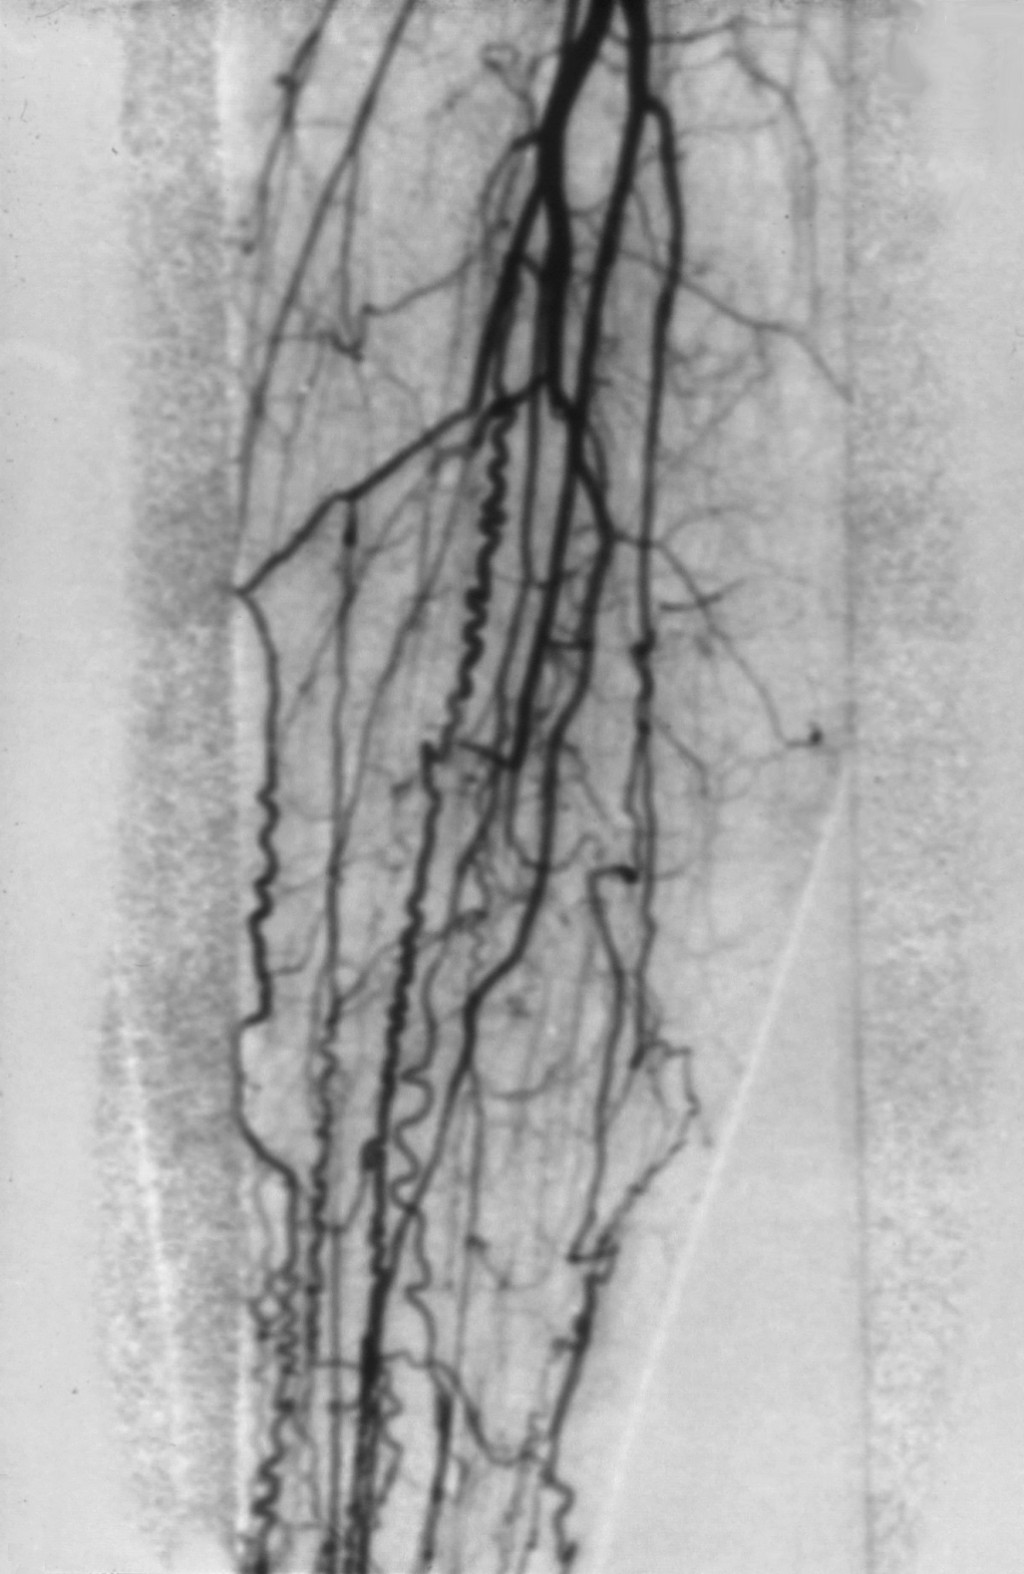

het in 1908 beschreef bij rokende Joodse mannen in New York. In het klassieke

geval kunnen op een arteriografie

spiraalvormige arteriën

(corkscrew vessels) zichtbaar zijn. De oorzaak is niet bekend.

![Ziekte van Buerger, tromboangiitis obliterans (click on photo to enlarge) [source: www.huidziekten.nl] Ziekte van Buerger, tromboangiitis obliterans](../../../images/tromboangiitis-obliterans-Buerger-2z.jpg) |

ziekte

van Buerger |

aan het ontstaan van atherosclerotische plaques. Typisch voor Buerger is dat

er (vrijwel) geen atherosclerotisch plaques zijn maar wel afsluiting van distale

arteriën, vaak korte segmenten, met vorming van collateralen die de typische

kurkentrekker vorm kunnen hebben.